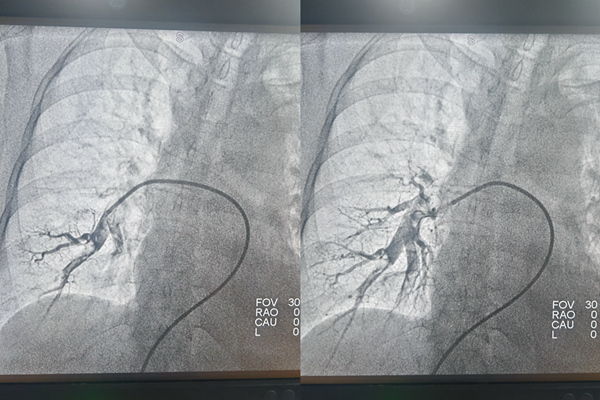

手術(shù)前后肺動脈造影對比。重慶兩江新區(qū)人民醫(yī)院供圖

孫曉龍通過患者雙側(cè)股靜脈穿刺,將一根如絲線般細的微導絲沿著血管送入雙側(cè)下肢靜脈進行造影。在X射線的實時監(jiān)控下,治療團隊仿佛擁有“透視眼”,能清晰看到導絲的位置和血管血流情況,顯示左側(cè)骼靜脈重度狹窄,并內(nèi)有血栓。沿著導絲再送入微導管進行造影,顯示左右兩側(cè)肺動脈內(nèi)均有血栓。

隨后,通過導管抽吸出血栓,疏通“堵點”,肺動脈血流即刻恢復暢通。接下來解決左側(cè)骼靜脈重度狹窄問題。治療團隊向左側(cè)骼靜脈送入細導絲,并沿導絲送入一個小小的球囊,將狹窄的血管擴張開來,再于血管狹窄處放置一枚支架,支撐起狹窄的血管壁,使血流重新通暢。